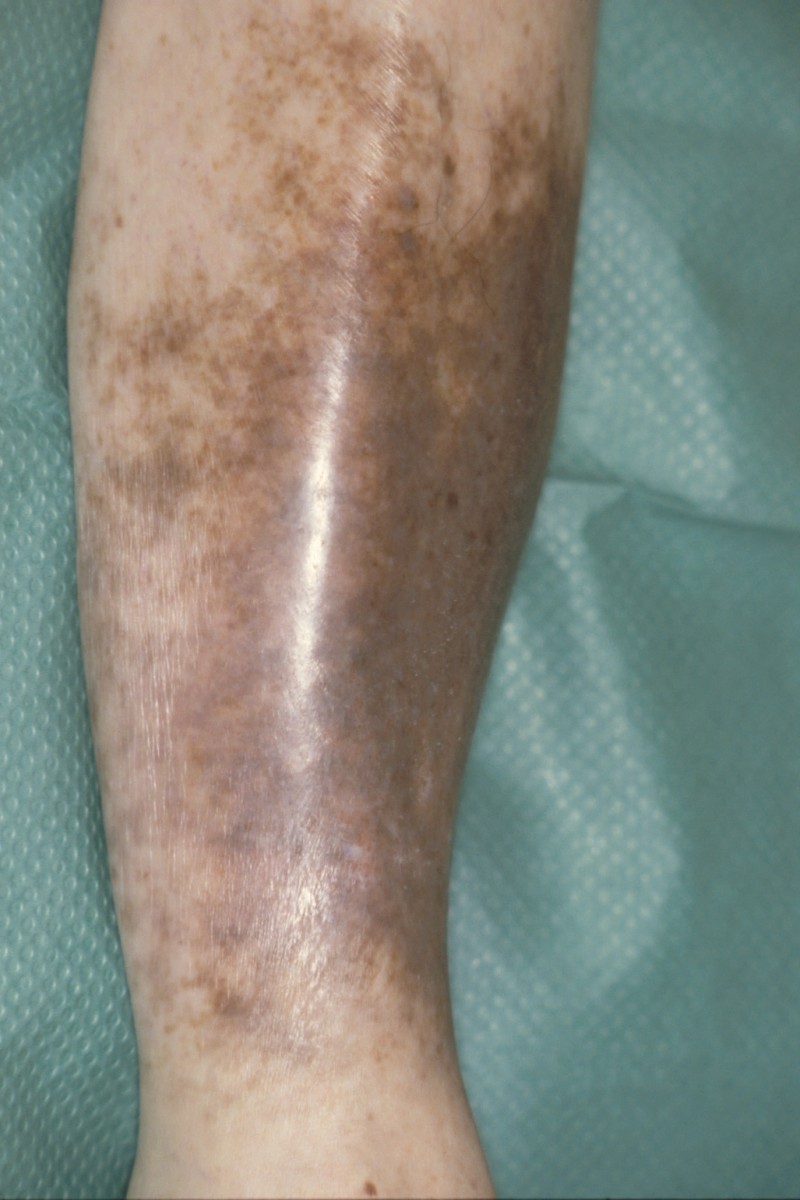

Hemosiderine pigmentatie

- hemosiderosis, het bruin ijzerhoudend pigment (hemosiderin) na erytrocyten extravasatie

- purpura jaune d'ocre (okergele-lichtbruine hemosiderine hyperpigmentatie bij veneuze insufficiëntie)